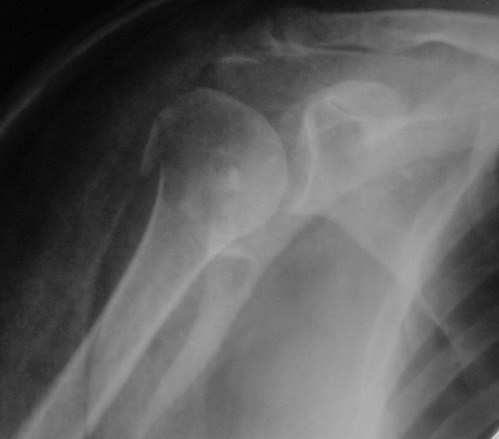

Снимки на 1-е сутки после репозиции и на 8- сутки после репозиции.

Пожалуйста

С ув. Sergey A. Melashenko, г. Запорожье